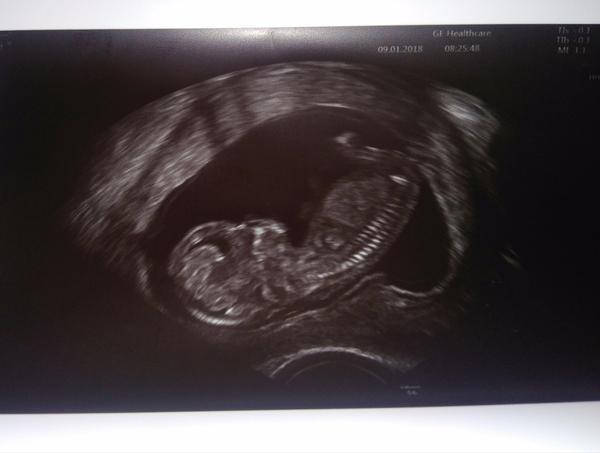

Ahoj holky jsem tu nová 🙂 ..Dnes jsme byli u mé paní doktorky a poprosili ji, aby se koukla jestli čekáme holčičku, nebo chlapečka, ale mimoušek tam měl stehýnko, zítra jdeme na ultrazvuk do nemocnice (2. část screeningu), kde se dozvíme výsledek krevního testu a taky doufáme, že se mimouš natočí a uvidíme pohlaví 🙂

@jancanunina ahojky, ano tatínek byl se mnou, teď už jsem podle PM 13+3 a podle dnešního UTZ 13+5 a minulý týden si paní doktorka už typla chlapečka tak uvidíme 🙂 Tatínkovi se to moc líbilo měl tam křesílko a před sebou obrazovku, kde viděl to co paní doktorka na monitoru 🙂